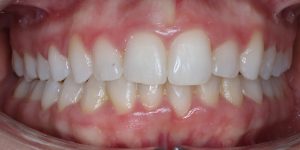

Maloclusión

Se caracteriza por una alineación incorrecta de los dientes, donde los dientes superiores e inferiores están en una relación normal, pero hay una falta de espacio que provoca que los dientes se solapen o estén apiñados.

Este problema puede generar dificultad para mantener una correcta higiene dental y afectar la estética de la sonrisa

INITIAL

22 Semanas de Tratamiento